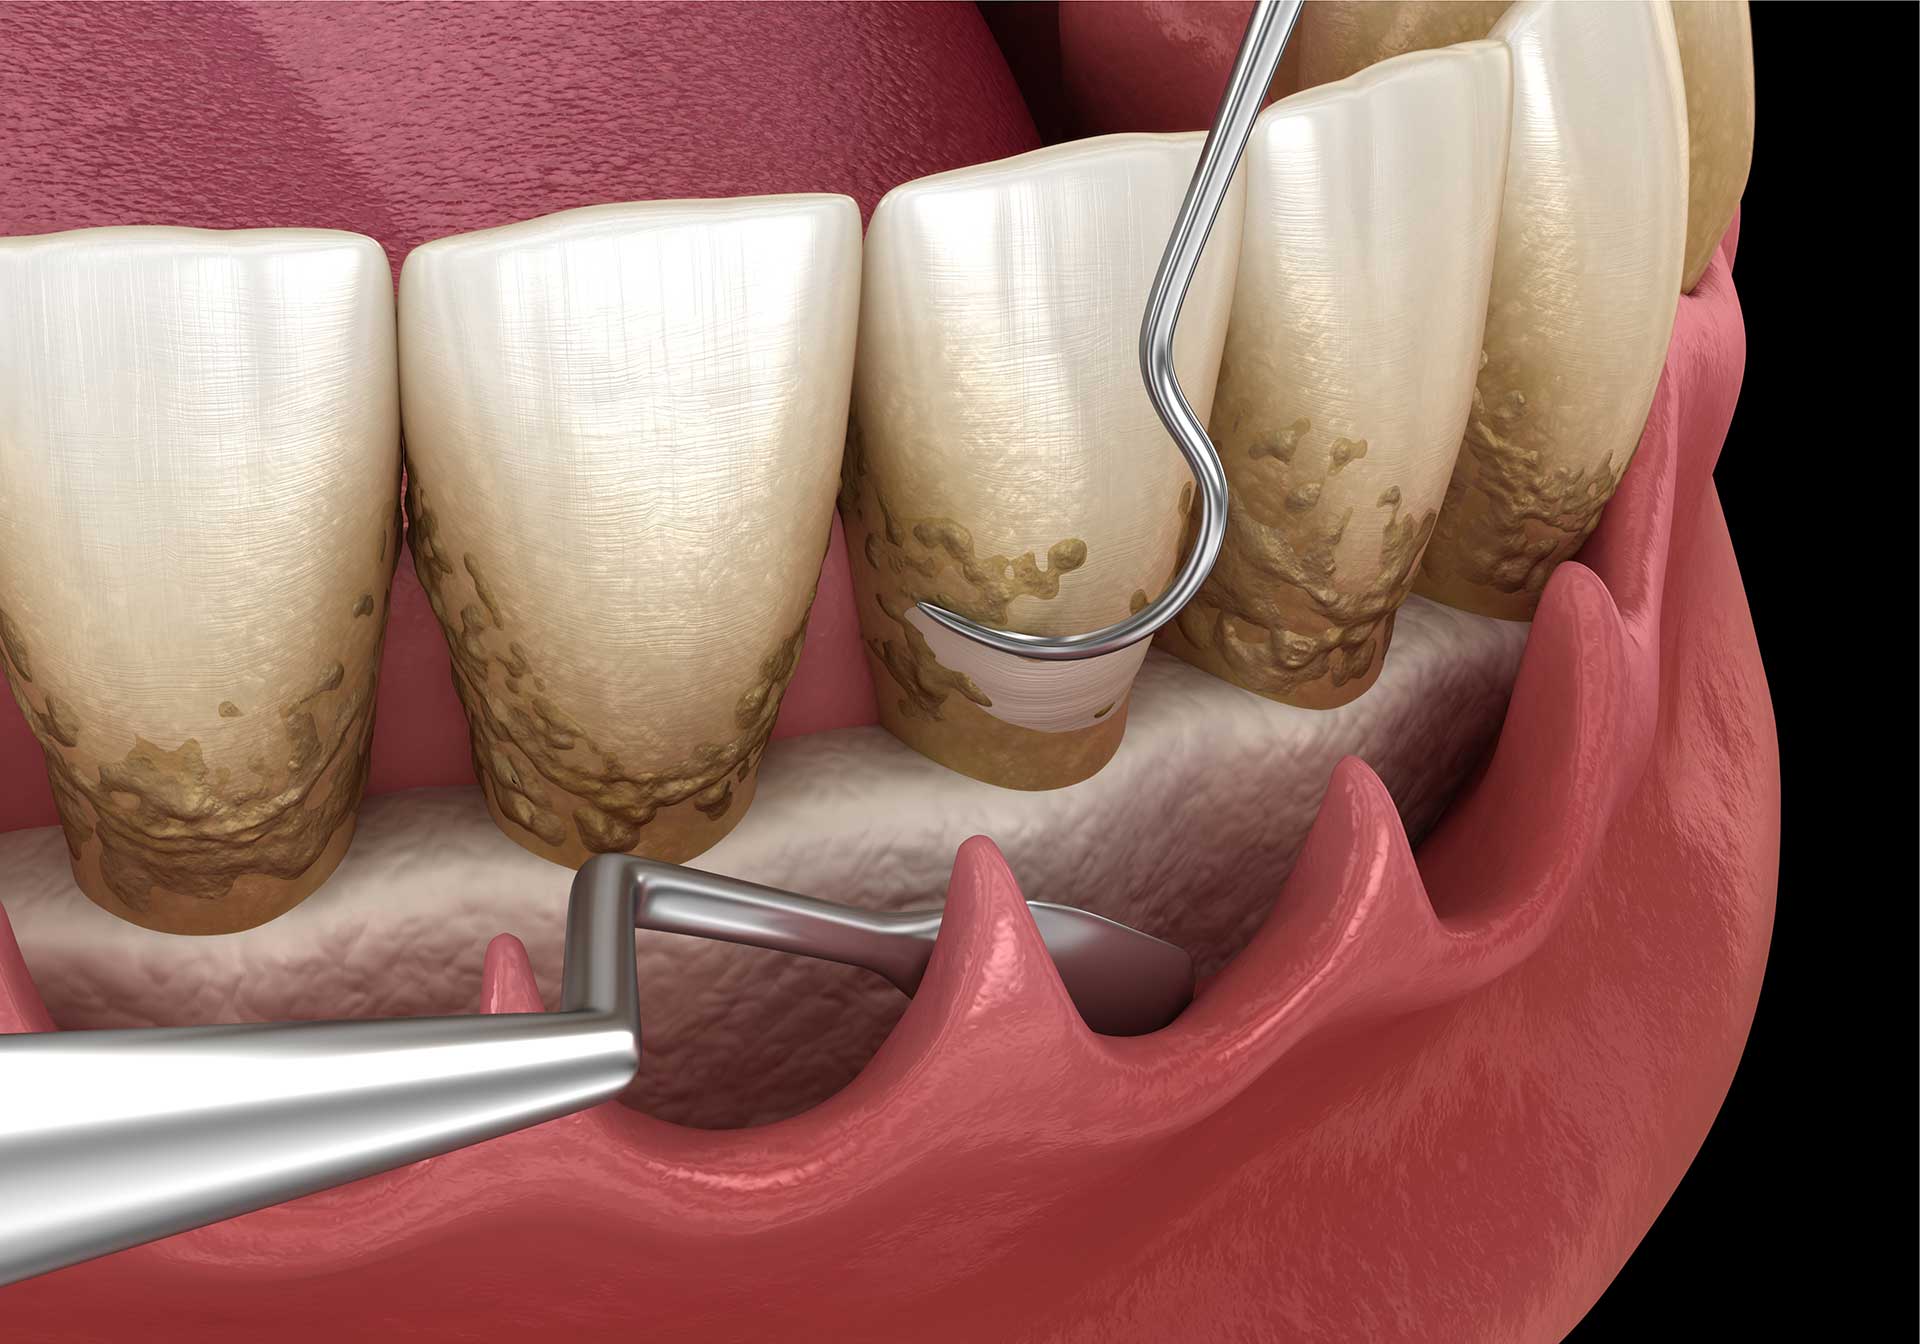

Occasional bad breath is common. Chronic halitosis that persists despite good oral hygiene is different. Bacteria living in deep periodontal pockets — the spaces between your teeth and gums that form as disease progresses — produce sulfur compounds that cause a distinctly unpleasant odor. No amount of mouthwash addresses the source.

If you're experiencing one or more of the above, the right step is a comprehensive periodontal evaluation. A periodontist is a specialist who focuses exclusively on the health of the structures that support your teeth — bone, gums, and connective tissue. A thorough exam includes pocket depth measurements, bone level assessment via X-rays, and a personalized treatment plan.

Early-stage gum disease (gingivitis) can often be managed with a professional cleaning and improved home care. More advanced disease may require scaling and root planing, surgical pocket reduction, or regenerative procedures. The sooner you come in, the more options are available — and the more of your natural teeth we can preserve.